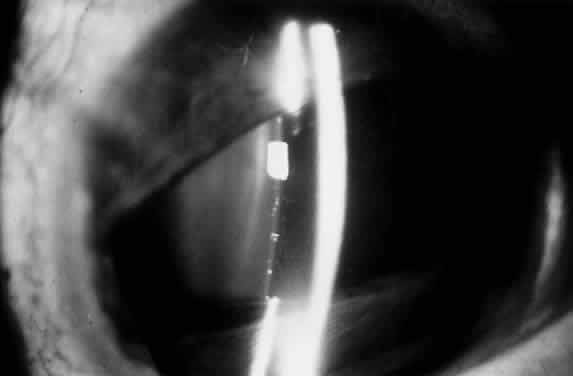

POSTERIOR LENTICONUS

Posterior lenticonus, which occurs more commonly than anterior lenticonus, is an ectasia of the posterocentral surface of the lens. It is often associated with progressive lens opacities of the posterior cortex. The majority of cases are unilateral, and the condition is found more frequently in females than in males. When no lens opacities are present, the clinical appearance of posterior lenticonus resembles the oil droplet appearance of anterior lenticonus. The characteristic localized posterior bulge can be seen with a slit lamp.4 The etiology of posterior lenticonus is unknown. Because the zonules exert traction on the lens and determine its shape, focal defective zonular traction along the posterior lens capsule may account for abnormal curvature in the area.